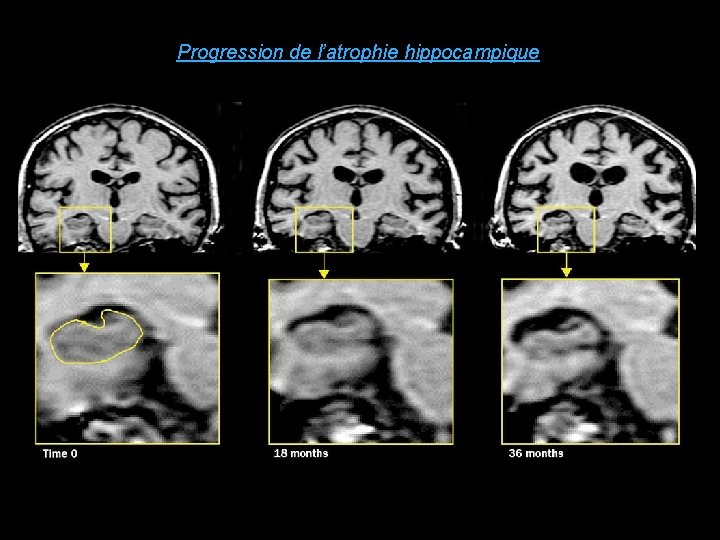

Progression de l’atrophie hippocampique